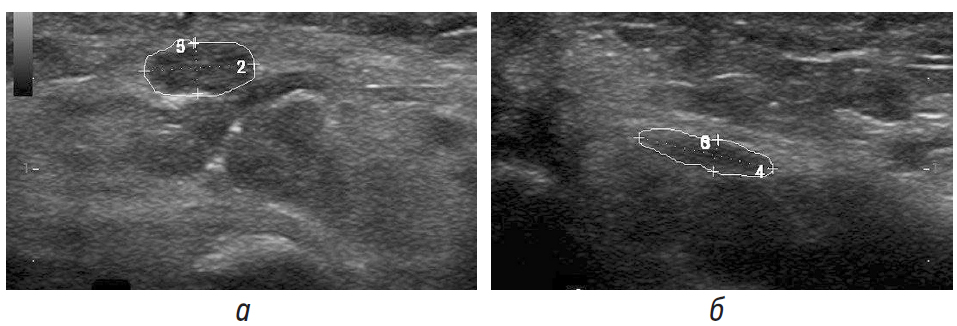

В соответствии с протоколом ультразвукового исследования при невропатиях PUEN, нашему пациенту поэтапно было выполнено исследование нервов верхних и нижних конечностей: на первом этапе с целью исключения вероятного диагноза ХВДП проводилась оценка ППС: 1) локтевого нерва на уровне канала Гийона; 2) локтевого нерва на уровне предплечья; 3) лучевого нерва на уровне спирального канала; 4) икроножного нерва. В связи с набранными баллами BUS — 0 баллов (менее 2 баллов), пациенту было выполнено исследование в соответствии со вторым этапом: 1) срединного нерва на уровне предплечья; 2) локтевого нерва на уровне предплечья; 3) большеберцового нерва на уровне лодыжки. В связи с выявлением утолщения левого большеберцового нерва на уровне медиальной лодыжки по данным УЗИ у пациента был диагностированный вероятный диагноз: ММН.

По данным УЗИ нервов верхних и нижних конечностей от декабря 2019 г.: ППС седалищного нерва на уровне нижней трети бедра: слева от 62 до 68 мм2, справа от 42 до 62 мм2. Норма: 42,4 + 13,2 мм2 [11]. Малоберцовый нерв неравномерной толщины, с наибольшим утолщением на уровне подколенной ямки, гипоэхогенный с увеличением отдельных фасцикул. Признаки сдавления на уровне малоберцового канала не определяются. ППС на уровне подколенной ямки: слева от 9 до 16 мм2, справа от 9 до 11 мм2. Норма [11]: 8,54 + 2,89 мм2. Большеберцовый нерв — неравномерной толщины, с наибольшим утолщением на уровне подколенной ямки и медиальной лодыжки, гиперэхогенный с увеличением отдельных гипоэхогенных фасцикул (больше слева). Признаки сдавления не определяются. ППС: слева от 35 до 43 мм2, справа от 37 до 43 мм2. Норма [11]: 23,7 + 5,7 мм2 (рис. 4).